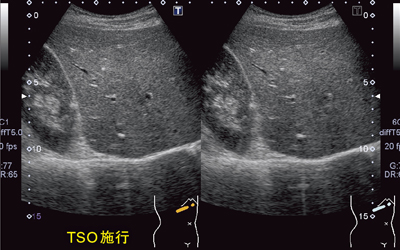

図5は,乳腺腫瘤の症例画像である。TSOを施行することで,方位分解能が向上し,腫瘤の輪郭や乳腺内部の構造がシャープに描出される。図6は,腋窩リンパ節腫脹の症例であるが,TSO施行により辺縁や内部の構造が明瞭に描出されるようになっている。高周波リニアにはAuto TSO機能が搭載されており,ボタン1つでTSO施行が可能である。

図5 乳腺腫瘤症例でのTSO施行例 脂肪組織の厚い乳房や腋窩などで有効である。

図5 乳腺腫瘤症例でのTSO施行例

脂肪組織の厚い乳房や腋窩などで有効である。

図6 腋窩リンパ節腫脹の症例 高周波リニアプローブにはAuto TSOが搭載されている。

図6 腋窩リンパ節腫脹の症例

高周波リニアプローブにはAuto TSOが搭載されている。